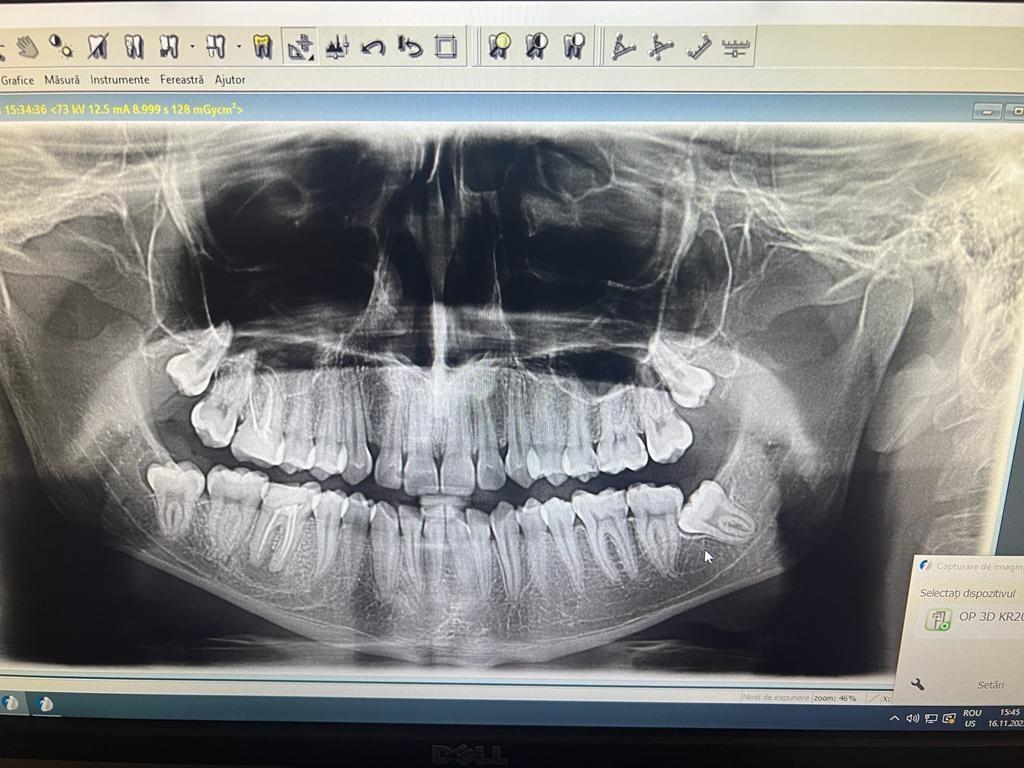

In urma unui consult dentar, medicul stomatolog stabileste primii pasi pentru implantul dentar: examen radiologic si analize de sange. La examenul radiologic se obtin informatii exacte despre cantitatea de os care urmeaza sa primeasca implantul dentar. Tot acum se poate stabili daca este nevoie de o eventuala aditie osoasa. Implantul se lasa in os intre 4 – 6 luni.